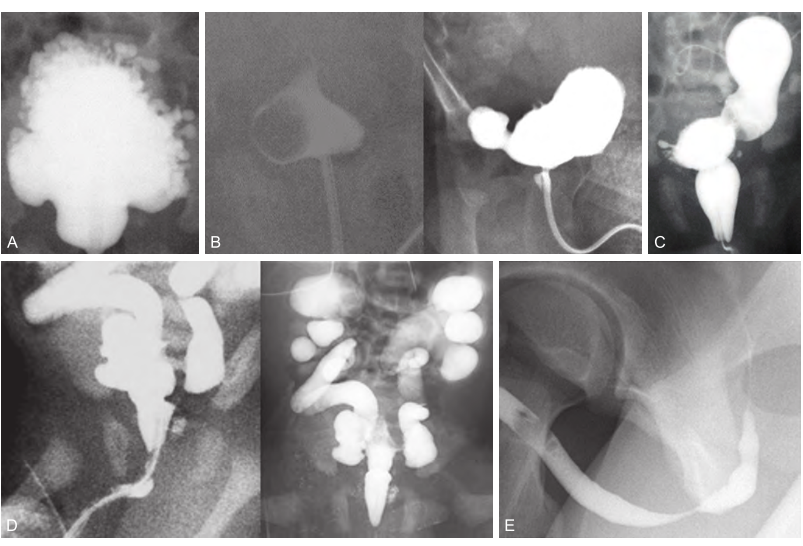

VCUG findings: identify A- E

(A) A highly trabeculated bladder. (B)

A ureterocele within the bladder (left) and then everting (right). (C) A large bladder diverticulum and elongated posterior urethra in a child with posterior urethral valve. (D) An elongated posterior urethra secondary to a posterior urethral valve and bilateral grade 5 vesicoureteral reflux. (E) A short distal bulbar urethral stricture.